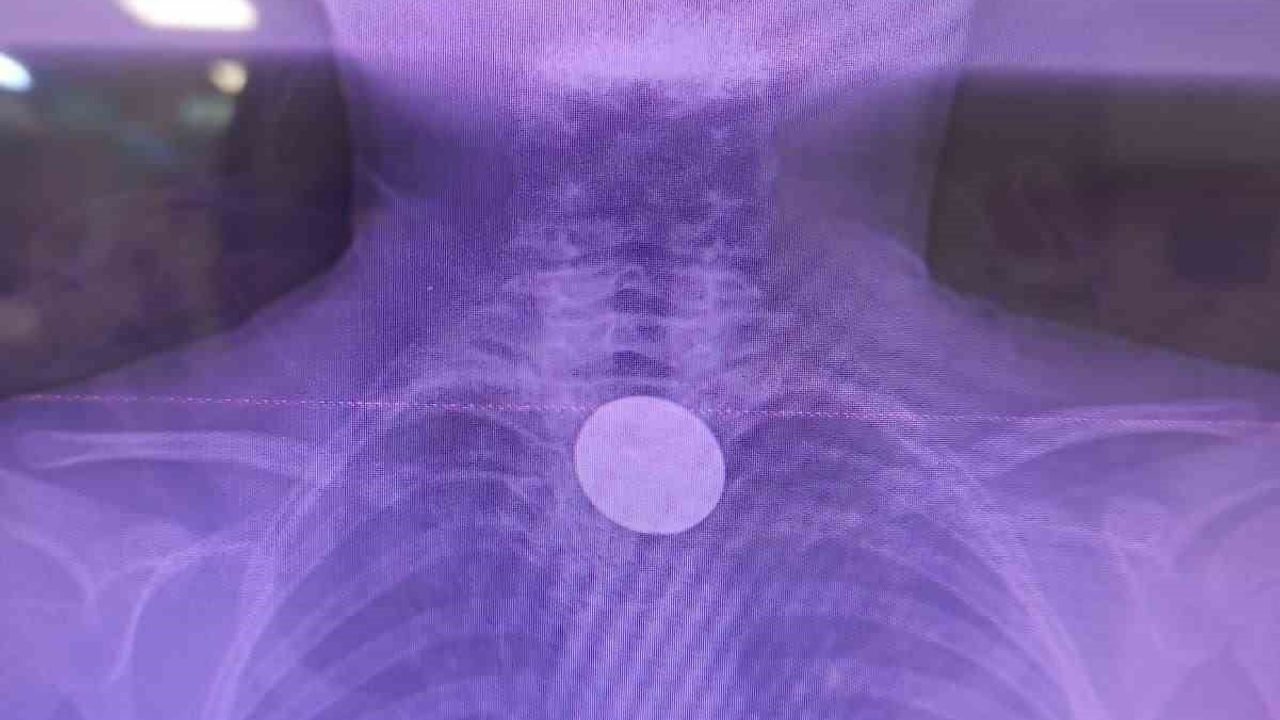

Siirt'te 8 yaşındaki Y.K., boğazına değeri 5 lira olan bir madeni para kaçması sonucu hastaneye başvurdu. Siirt Eğitim ve Araştırma Hastanesi'nde yaşanan bu olay, doktorların hızlı müdahalesi sayesinde başarılı bir şekilde sonuçlandı.

Yabancı Cisim Yutma Gerçeği

Ailesi tarafından hastaneye getirilen çocuk, yabancı cisim yutma şikayeti ile acil servise alındı. Yapılan detaylı incelemeler sonucunda, madeni paranın yemek borusuna kadar ilerlediği belirlendi. Uzman ekip, gastroenteroloji doktoru Dr. Yaren Dirik ve kulak burun boğaz hekimi Yasin Gökçınar tarafından gerçekleştirilen operasyonla para çıkarıldı.